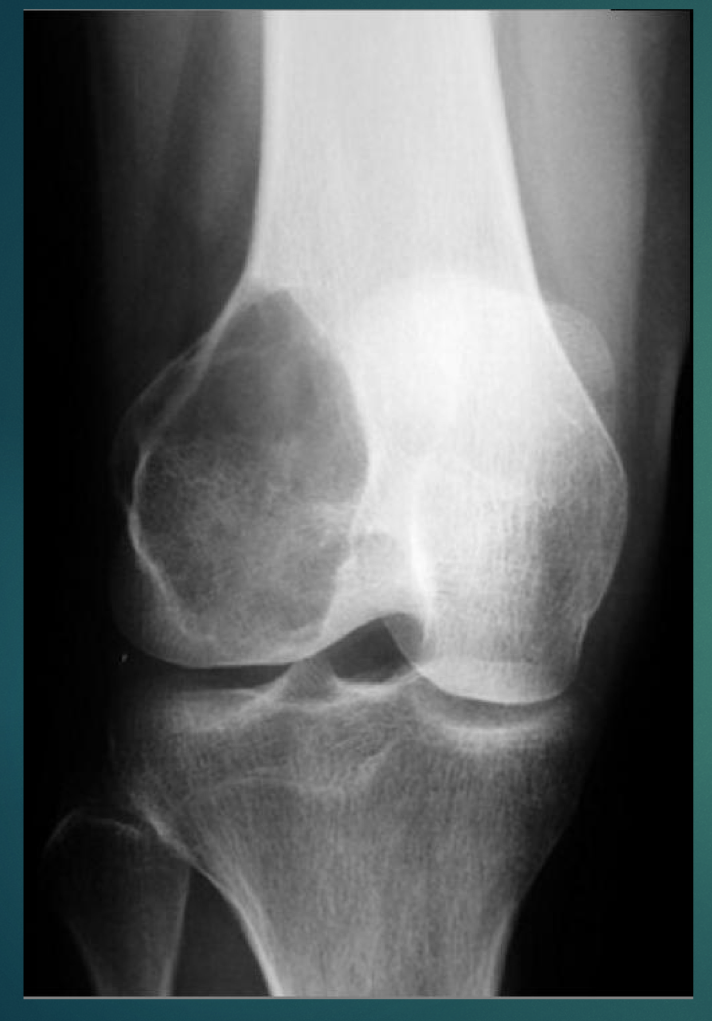

28 YO M. No history provided.

• Lytic, soap bubbly

• Closed growth plates

• Location at the knee

Think: Giant Cell Tumor